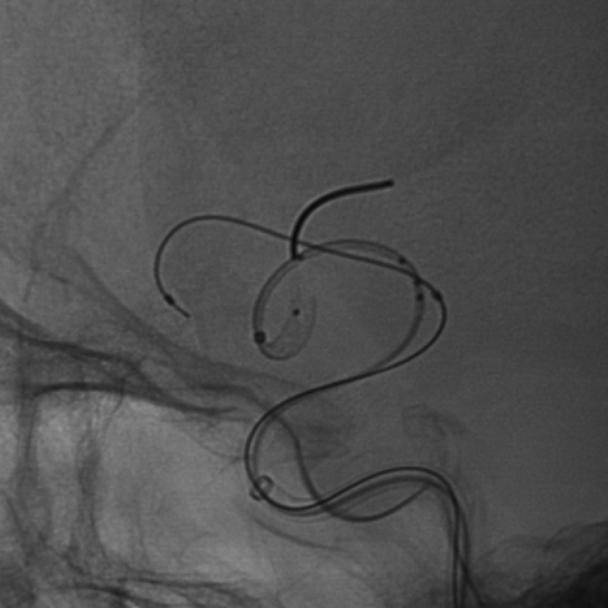

手术过程

微导丝、微导管到位:

通路建立完成后,微导丝瘤内成袢,超选至大脑中动脉远端,支架微导管到位。

弹簧圈微导管到位。

Lattice释放:

Lattice输送到位后,透视下将支架远端定位于大脑中动脉远端,回撤微导管原位释放支架,可见在支架头端机械球囊的辅助下,支架远端打开良好,头端导丝不位移。继续释放支架至尾端,回撤微导管,支架自然打开贴壁满意,回撤球囊。

释放弹簧圈:

支架释放后,使用弹簧圈微导管释放弹簧圈,填塞动脉瘤。